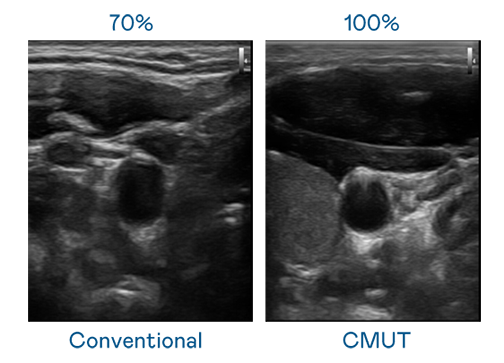

CMUT 技术是一种用电容式微机电元件来产生超音波讯号的技术。与传统 PZT 压电式技术相比,CMUT 频宽增加 30%,更宽频的超音波讯号让影像解析度大幅提升,是实现高影像品质医疗超音波扫描、促进精准医疗发展的关键技术。

超音波影像的解析度高低,首先取决于探头能发出的讯号频宽。乐天使 CMUT 可提供高清晰的超音波讯号,提供高频宽、高灵敏度、影像纹理细节更高的超音波影像,协助医护人员缩短影像判读时间及利用精准的医疗影像进行诊断。